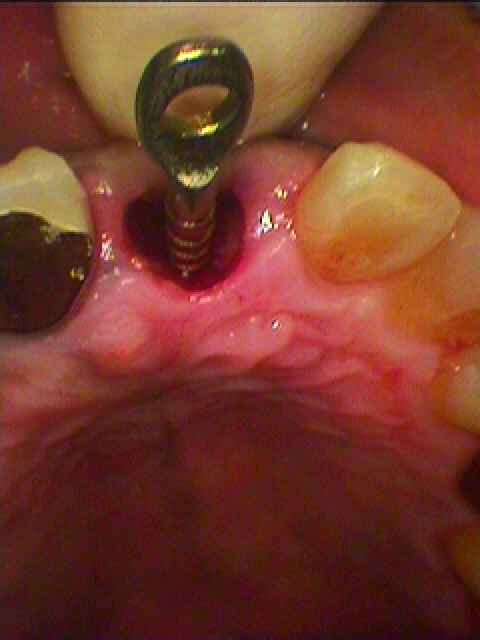

左上前歯部の歯牙破折により抜歯即時インプラント埋入へ 40代男性|お知らせ |広島市安佐南区の歯科医院 左上前歯部の歯牙破折により抜歯即時インプラント埋入へ 40代男性 トップ お知らせ・ブログ お知らせ 左上前歯部の歯牙破折により抜歯即時インプラント埋入へ 40代男性 左上前歯部の歯牙破折により抜歯即時インプラント埋入へ 40代男性 歯質も破折だ毛ではなく柔らかく弱くなっていました 抜歯を行っています 抜歯窩になります 最初のガイドピンを建てて方向、深度、埋入位置をCTにて 確認していきます 最初の埋入窩になります 最終インプラント埋入時になります 隙間には骨補填材を転入していきました 縫合して仮歯をレスカンツァーにてセットしています これにて2か月待っていきます Web診療予約 初めての方へ 選ばれ続ける理由 院内設備について 歯が痛いしみる一般歯科 歯がぐらぐらする歯周病 健康な歯を保ちたい予防歯科 子供の虫歯予防をしたい小児歯科 銀歯をセラミックに審美歯科 白い歯を目指しませんか?ホワイトニング 矯正専門医がいるので安心矯正歯科 抜けた歯を補いたいインプラント・入れ歯 医院案内 スタッフ紹介 メリィハウス歯科クリニックオフィシャルホームページ ラベンダー歯科クリニックオフィシャルホームページ お知らせ・ブログ ホーム 診療科目 一般歯科 歯周病治療 予防治療 小児歯科 審美治療 ホワイトニング 矯正歯科 入れ歯・インプラント マウスピース矯正 初めての方へ 院長・スタッフ 設備紹介 医院案内・アクセス メニューを閉じる